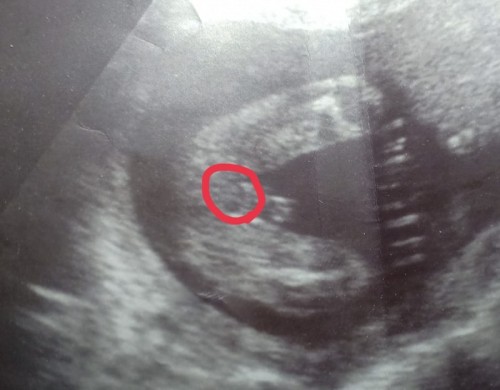

ช่วยดูหน่อยค่ะ บางทีนึกว่าเพศหญิง

น้องเป็นผู้ชายหรือผู้หญิงค่ะ หมอบอกว่าชาย คุนแม่กังวลว่าน้องจะเป็นเพศหญิงค่ะ

บ้านนี้ชายชัดเจนมากค่ะ รูปก็คล้ายๆของคุณแม่อยู่นะคะ ในใจอยากได้ลูกสาวเพราะมีชาย2แล้ว😅 แต่ไม่เป็นไร ยังไงก็ลูก รักหมดใจ